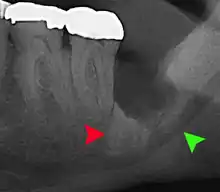

For partially impacted teeth in those over 20 year of age, the most common pathology seen, and the most common reason for wisdom teeth removal, is pericoronitis or infection of the gum tissue over the impacted tooth. The bacteria associated with infections include Peptostreptococcus, Fusobacterium, and Bacteroides bacteria. The next most common pathology seen is cavities or tooth decay. Fifteen percent of people with retained wisdom teeth exposed to the mouth have cavities on the wisdom tooth or adjacent second molar due to a wisdom tooth. The rate of cavities on the back of the second molar has been reported anywhere from 1% to 19% with the wide variation attributed to increased age.[12]

In five percent of cases, advanced periodontitis or gum inflammation between the second and third molars precipitates the removal of wisdom teeth.[5]: 141 [6] Among patients with retained, asymptomatic wisdom teeth, roughly 25% have gum infections (periodontal disease).[13]: ch13 Teeth with periodontal pockets of greater than 5mm have tooth loss rates that start at 10 teeth lost per 1000 teeth per year at 5mm to a rate of 70 teeth lost per year per 1000 teeth at 11mm.[14]: 57 The risk of periodontal disease and caries on third molars increases with age with a small minority (less than 2%) of adults age 65 years or older maintaining the teeth without caries or periodontal disease and 13% maintaining unimpacted wisdom teeth without caries or periodontal disease.[15] Periodontal probing depths increase over time to greater than 4 mm in a significant proportion of young adults with retained impacted wisdom teeth which is associated with increases in serum inflammatory markers such as interleukin-6, soluble intracellular adhesion molecule-1 and C-reactive protein.[16]